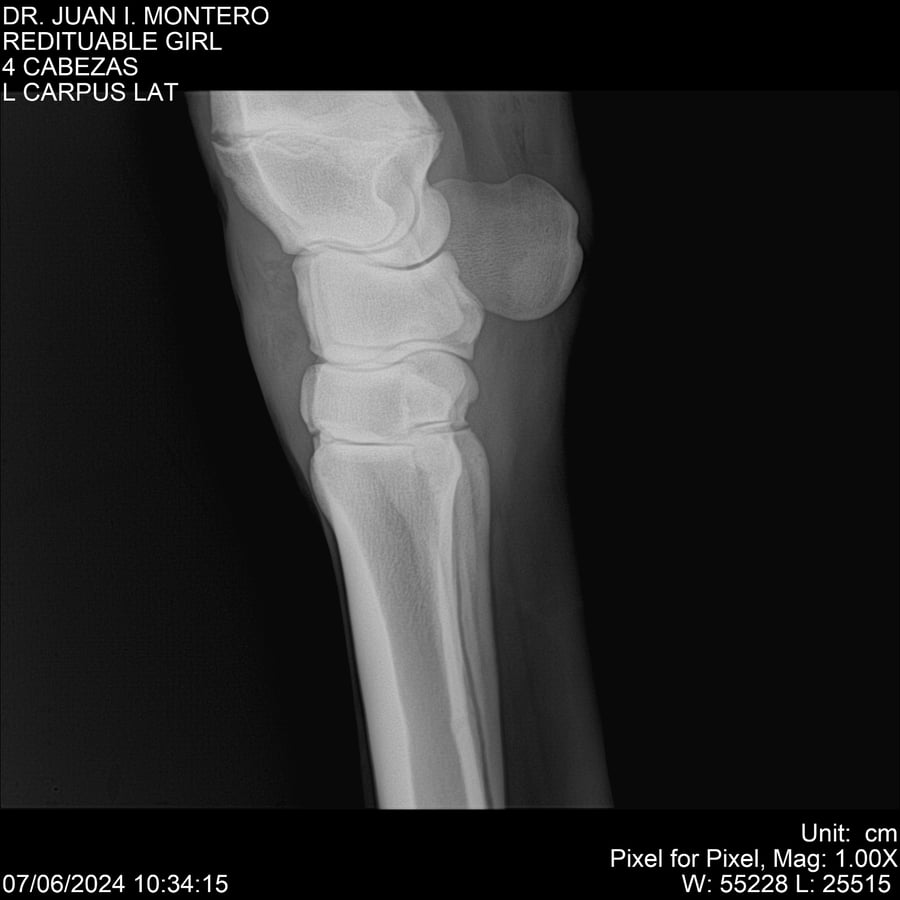

LOTE 19, REDITUABLE GIRL Lote Anterior Volver al remate Lote Siguiente Ficha Contacto Montevideo - Ficha del Lote Identificador: #281096 Categoría: Yeguarizos Montevideo - 79 Visualizaciones ClicData Contacto Empresa: Abelenda N. R., Walter Hugo Nombre*: Teléfono* : E-mail* : Mensaje Enviar Registrese gratis Este contenido Exclusivo está disponible sólo para usuarios registrados Ingresar